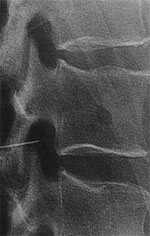

Diagnostic and therapeutic injections of the nerve roots are performed for diagnostic purposes and also when combined with steroids for permanent/semi-permanent pain relief.